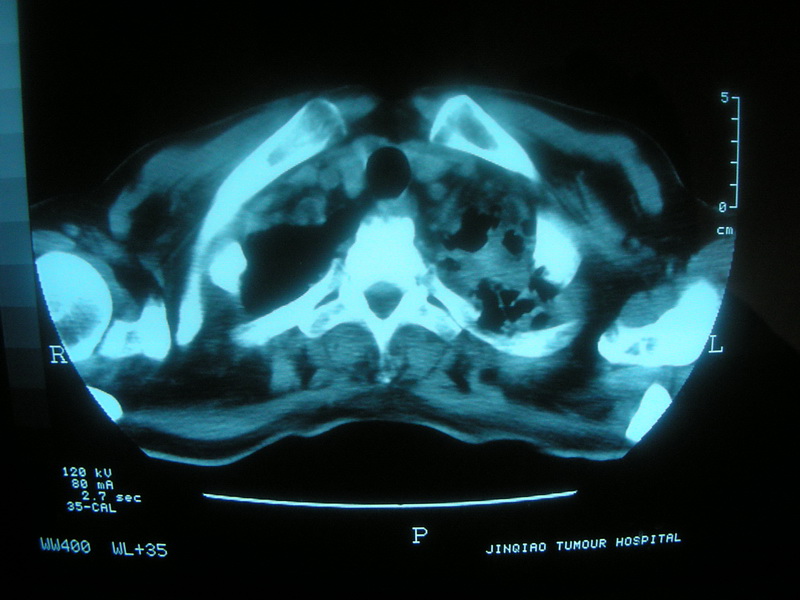

标题: CT11692:男,63岁,糖尿病史15年.抗炎治疗7天,病情 [打印本页]

标题: CT11692:男,63岁,糖尿病史15年.抗炎治疗7天,病情

请老师看看是结核还是炎症?

根据影像表现及临床符合结核感染。

双肺继发性肺结核伴感染!